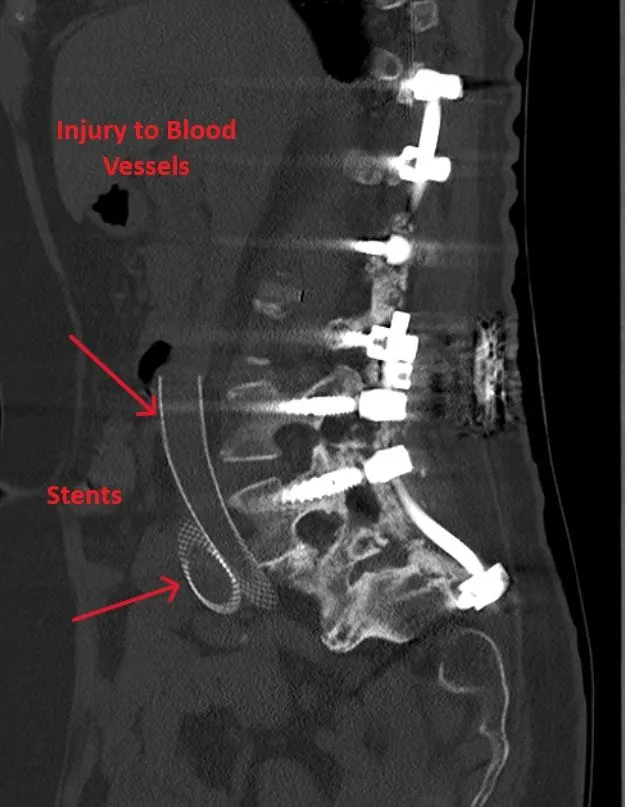

CT scan showing spinal hardware with labeled blood vessel injury and stents.

Vascular, Bladder & Ureter Injury

Injury to major blood vessels, bladder, or ureters during the anterior surgical approach.